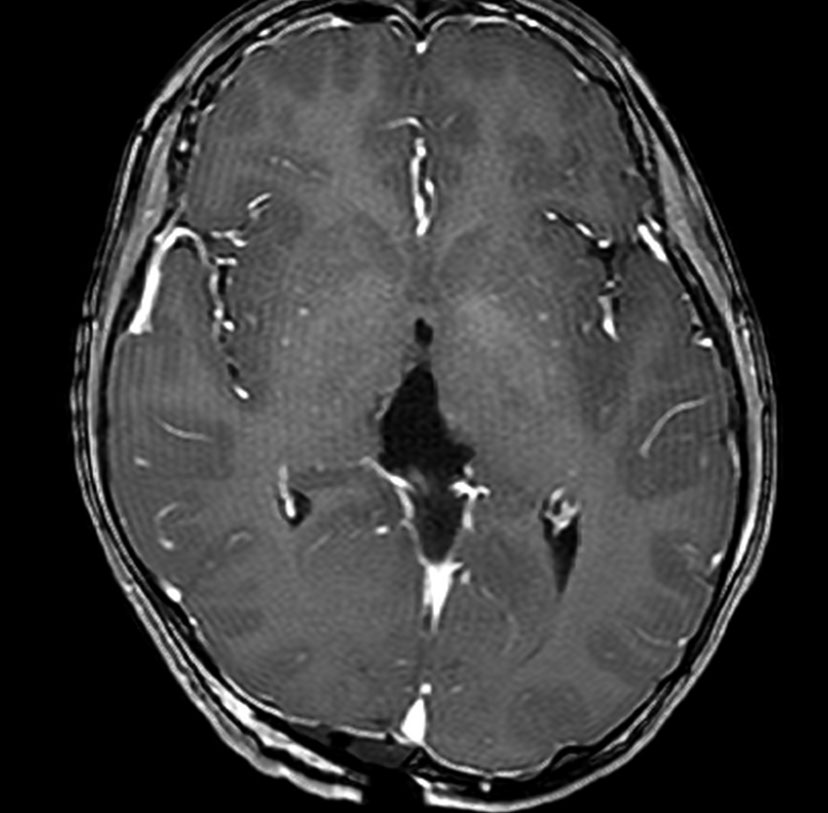

MRIです

左の拡散強調画像で高信号となり類表皮のう胞 epidermoid cyst あるいは類皮のう胞 dermoid cyst の診断です。しかし右のT2強調画像では左後方に違う信号の腫瘍塊があります。

ガドリニウム増強像です。類皮のう胞(成熟奇形腫 mature teratoma)との混合性胚細胞腫瘍を強く疑う所見です。